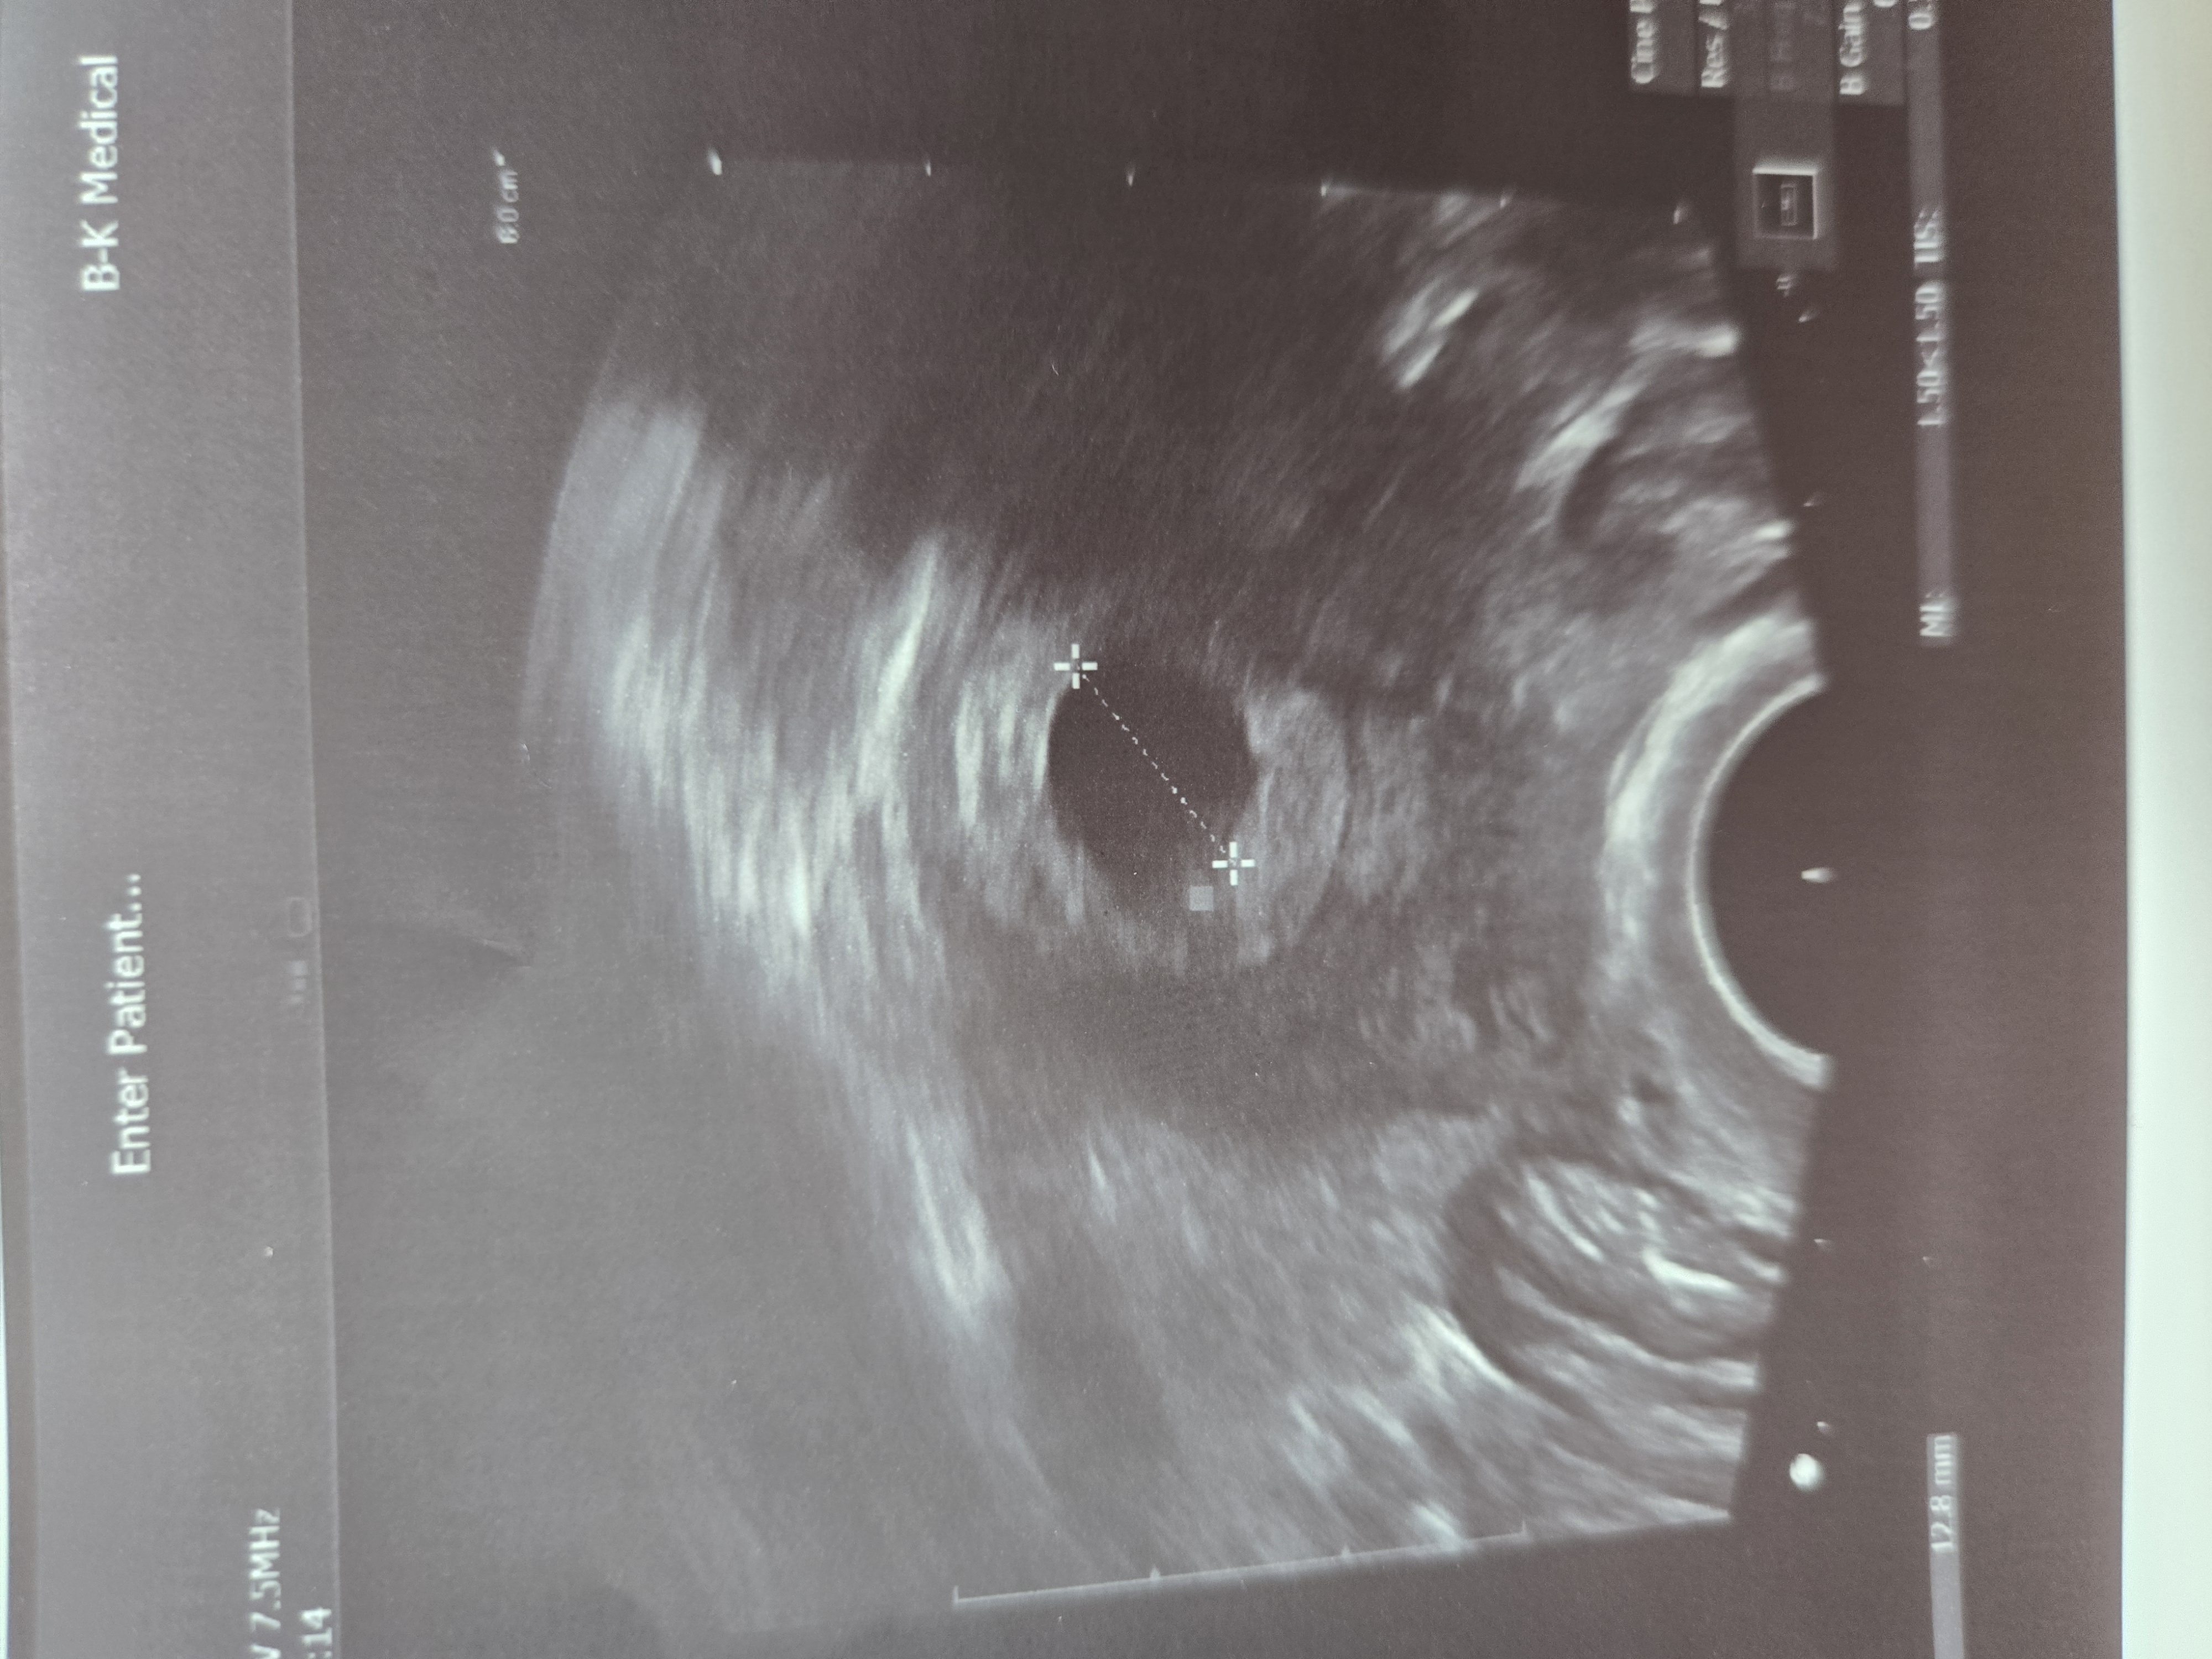

Узи 23 ДПП

В полости матки:

Средний диаметр 13 ММ

КТР 3 ММ

Желточный мешок 3 ММ

Пригласили на повторное узи 10го марта слушать сердцебиение. Сегодня оно просматривается но конечно ещё ничего не послушать )